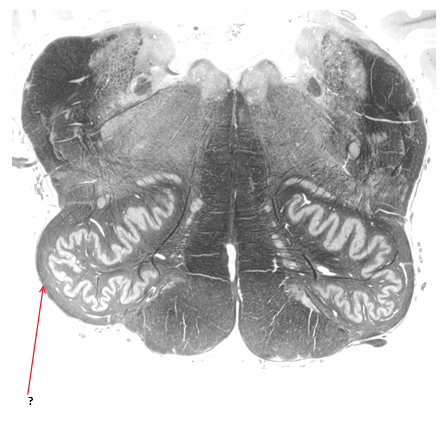

Name this and state its function.

Inferior cerebellar peduncle.